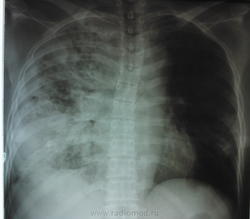

сегодня пациентке провели контрольную R-графию (снимок только в прямой проекции и на другом аппарате - немного "мягче", предыдущий сломался, а этот боковой не смог снять), сравнить тяжело (на разных аппаратах, разная экспозиция и тд и тп) но по мне динамика отрицательная.

из анализов: изменения только в ОАК от 7.07.2013 СОЭ повысилась до 35 мм\ч, лейкоциты по прежнему в норме - 8,8

мокроту со слов лечащего врача собрать не удалось, ее просто нету, редкий непродуктивный кашель, температура тела в пределах нормы все это время

провели кт: заключение по КТ ОГК - картина деструктивной полисегментарной пневмонии правого легкого, и сегментарной нижней доли левого, КТ ОБП - картина жировой дистрофии печени, киста левой почки. Сами снимки мне увидеть не удалось - родственники зачем то увезли в деревню, надеюсь привезут на днях и я хотя бы их сфотографирую для вас.

перестала самостоятельно ходить, возят ее на кресле, а ведь еще неделю назад сама приходила на R графию, теперь стоит при поддержке других. внешне опять таки никаких проявлений - разве только вялой стала.